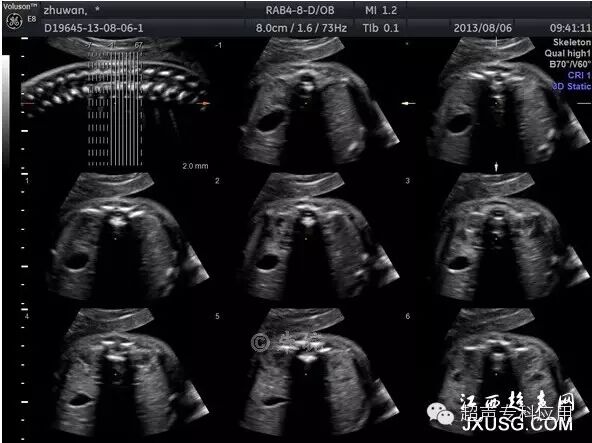

1.4 多平面断层扫查 这种三维超声形式与CT断层扫描相似,连续平行的断面图,就如慢慢平行移动探头,将检查部位从上至下或从左到右显示一遍。每幅断面图之间的距离可以调节,间隔或较宽、或较窄。连续平面可以是横切,可以是纵切,也可以是冠状切。这一技术在胎儿颅脑及心脏的检查中应用较广,如颅脑横切面或冠状切面的连续多平面检查。

胎儿脊柱三维多平面断层成像(TUI)

胎儿头部三维多平面断层成像(TUI)